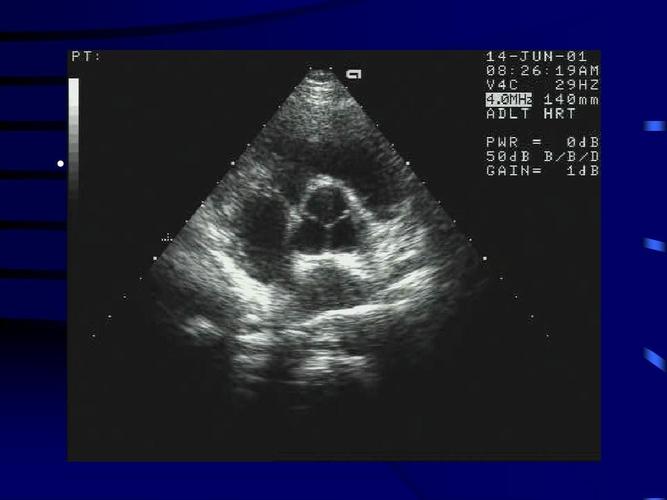

正常超声心动图

正常超声心动图,超声心动图正常值

正常超声心动图-超声诊断学

超声心动图

二维超声心动图